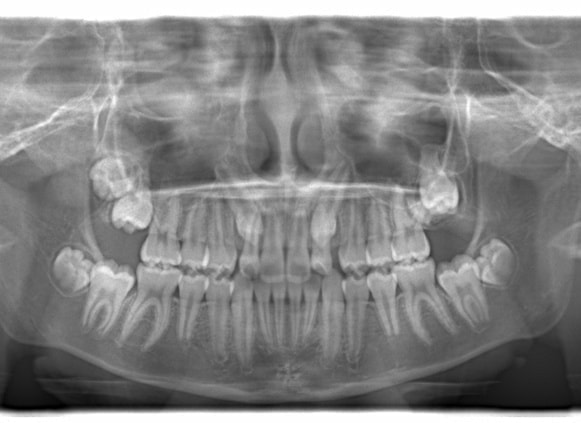

治療前

治療開始時

FX(フェイシャルアキシス)は85度なので東洋人の平均値に近く、下顎が前方に過剰成長するリスクは強くはありません。

しかしやはり上顎は劣成長で、下顎が優位な状態ではあります。

上下顎のギャップはありますが、顔面自体の幅径は良好な値を示していますので、スペース不足は拡大することによって解決できポテンシャルはあると考えられます。

左右の非対称もさほど強くありません。

骨年齢は実年齢よりも低めなので、今後下顎の旺盛な成長が見込まれます。

検査時のレントゲン分析では、上下顎の関係は、上顎の劣成長があり下顎前突傾向という値がでておりましたが、前歯ジャンプ後はフェイスマスクの効果もあり、上下顎の関係は正常化しています。

上顎が若干優位になっていますので、今後の下顎の成長のための貯金になっているくらいです。